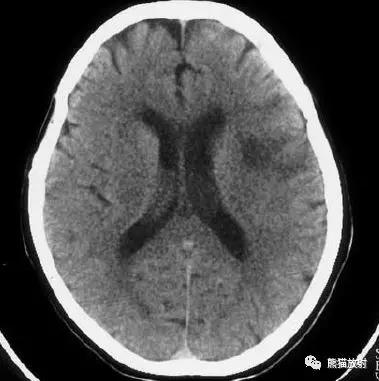

大脑中动脉区梗死:部分梗死,仅累及左侧浅表区域。

左侧大脑中动脉区完全梗死,对邻近的侧脑室产生占位效应;右侧可见其他较小的缺血性低密度区。

右侧大脑前动脉供血区部分梗死

右侧大脑后动脉供血区梗死

双侧大脑后动脉供血区梗死